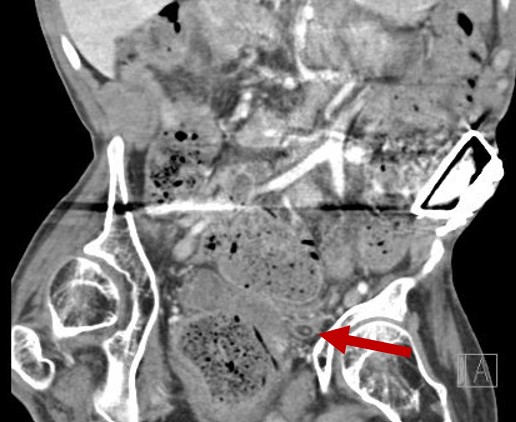

catheter image 2 oct 2024